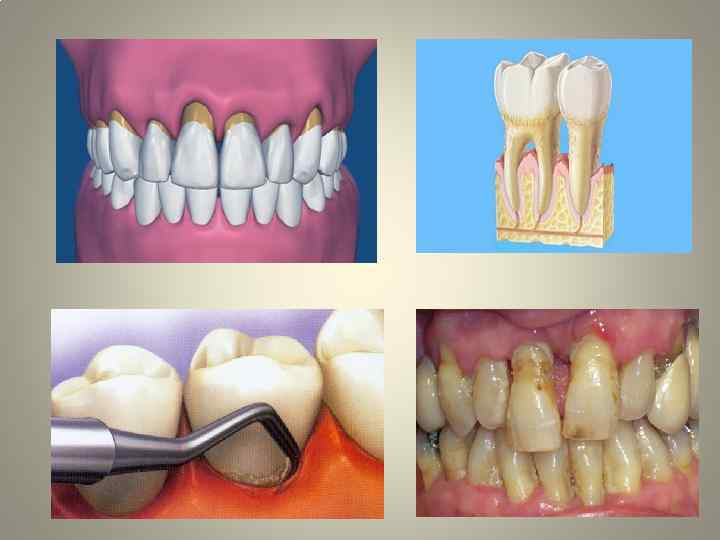

• • • пародонтит – заболевания воспалительно деструктивного характера, при котором воспаление десны распространяется на подлежащие ткани и сопровождается прогрессирующим разрушением периодонта и костной ткани вначале межзубных, а в последующем и межкорневых перегородок и других отделов альвеолярного отростка при активном течении заболевания характерны следующие признаки: заболевание выявляется преимущественно у лиц в возрасте старше 30 лет; из анамнеза выясняется наличие кровоточивости десен в течение многих лет; обнаруживается воспаление десны с преобладанием серозного (катарального), некротического или пролиферативного процесса, т. е. так называемый симптоматический гингивит; выявляется клинический карман различной глубины. Это – первый основной признак заболевания; на внутриротовой рентгенограмме альвеолярных отростков, ортопантомограмме, панорамной рентгенограмме челюстей обнаруживается резорбция костной ткани второй основной признак. Рентгенологические изменения проявляются наличием деструктивных изменений костной ткани межзубных перегородок (а при прогрессировании процесса – и в области межкорневых перегородок, бифуркации) без нарушения глубоких отделов альвеолярного отростка и тела челюстей. , в отличие от пародонтоза, эти изменения, как правило, носят локальный характер, не затрагивая других костей скелета; выявляется разнообразная клиническая симптоматика, обусловленная выраженностью воспалительной деструкции костной ткани и периодонта, а также клинико морфологической картиной воспаления десны: расшатывание (подвижность) зубов (третий основной признак пародонтита), их смещение, боль, нарушение функции, травматическая артикуляция и др. ; нередкими являются обострения хронического пародонтита и особенно гнойный и абсцедирующий пародонтит, которые сопровождаются выраженными общими нарушениями: повышением температуры тела, недомоганием, слабостью, изменениями периферической крови по типу реакции на неспецифический воспалительный процесс (лейкоцитоз, сдвиг лейкоцитарной формулы влево, увеличение СОЭ и др. ); имеют место значительные отложения назубного налета (т. е. над и поддесневого «зубного камня» )

• • • • В соответствии с тяжестью клинических проявлений выделяют пародонтит легкий, средней тяжести и тяжелый. Такое деление удобно для выбора вида хирургического, ортопедического вмешательств и всей комплексной терапии в целом. Для легкого пародонтита характерны: глубина пародонтального кармана до 3, 5 мм, преимущественно в области межзубного промежутка; начальная степень деструкции костной ткани по рентгенограмме (отсутствие компактной пластинки на вершине и боковых отделах перегородки, очаги остеопороза, расширение периодонтальной щели в пришеечной области); зубы неподвижны, не смещены; общее состояние пациента не нарушено. При пародонтите средней степени тяжести: глубина пародонтального кармана достигает 5 мм; имеет место резорбция костной ткани по рентгенограмме на одну треть или на половину межзубной перегородки; подвижность зубов I II степени с возможным смещением их. Тяжелая степень пародонтита характеризуется: глубиной пародонтальных карманов более 5 6 мм; деструкцией костной ткани альвеолярного отростка более, чем на половину или полным отсутствием костной ткани; патологической подвижностью зубов преимущественно II III степе ни, их смещением, выраженной травматической артикуляцией.

• • Тяжелый пародонтит и пародонтит средней степени тяжести часто сопровождаются гноетечением из пародонтальных карманов и абсцедированием. Своеобразная клиническая картина последнего (необходимо отличать от острого гнойного периостита челюсти), наклонность к рецидивам, возникновение пародонтальных абсцессов то в одном, то в другом участке зубной дуги характеризуют это заболевание. Особенно часто пародонтальные абсцессы наблюдаются при фоновой патологии (например, при сахарном диабет). Следует отметить, что при наличии оттока экссудата и гноя из пародонтального кармана абсцедирование обычно не возникает. При абсцедировании, кроме отчетливо выявляющихся местных признаков гнойного воспаления (в первую очередь десны), усиления подвижности зубов определяются также симптомы общей интоксикации организма больного. Все описанные признаки заболевания относятся к пародонтиту в стадии активного течения, т. е. в той стадии, с которой больной обращается к врачу (пародонтит нелеченный или лечение его проведено не рационально или не в полном объеме).